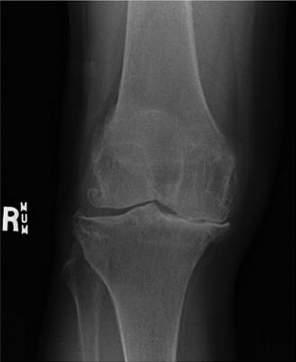

’ Plainradiographoftherightknee

Theplainradiographsoftherightkneerevealedsignificantjointspacenarrowingandosteophyteformationconsistentwithsevereosteoarthritis(Fig.1.1).

Fig.1.1 Osteoarthritisoftheknee.AnteroposteriorstandingkneeX-raywithjointspaceloss,especiallyinthemedialcompartmentandosteophytesbilaterally.(FromVincentTL,WattFE.Osteoarthritis. Medicine.2018:46[3]:187 195[Fig.3C].)

Plainradiographyisindicatedinall patientswhopresentwithkneepain (Fig.1.6).Basedonthepatient’sclinicalpresentation,additionaltestingmay bewarranted,includingacompletebloodcount,erythrocytesedimentation rate,andantinuclearantibodytesting.Magneticresonance(MRI)andultrasoundimagingofthekneeisindicated ifinternalderangement,aseptic necrosis,oranoccultmassortumoriss uspected,orifthediagnosisisin question( Figs.1.7 and 1.8).

Fig.1.6 X-raysofosteoarthritisoftheknee:(A)grade0normal,(B)grade1lateralfemoralosteophyte,(C)grade2lateralfemoralosteophyte,and(D)grade3lateralfemoralosteophyte.(From AltmanRD,GoldGE.Atlasofindividualradiographicfeaturesinosteoarthritis,revised. Osteoarthr Cart.2007:15[1]:A1 A56[Fig.22].)